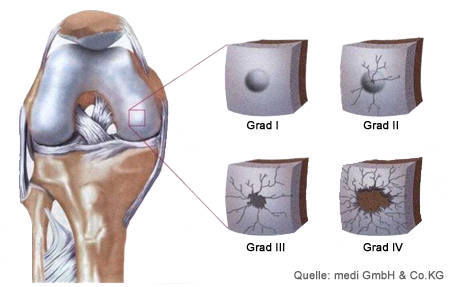

Οι χόνδρινες βλάβες συνήθως δεν αυτοθεραπεύονται γιατί ο χόνδρος δεν έχει αγγειακή αιμάτωση και δυστυχώς έχει ελάχιστη αναγεννητική ικανότητα, οι βλάβες ταξινομούνται σε 4 τέσσερα στάδια:

- Στάδιο 1: μικρές αναστρέψιμες βλάβες της κυτταρικής δομής του χόνδρου

- Στάδιο 2: μικρές βλάβες σχισμές στην επιφάνεια του χόνδρου μικρότερες ή ίσες με το 50% του πάχους του χόνδρου

- Στάδιο 3: βλάβες που υπερβαίνουν το 50% του πάχους του χόνδρου και είναι ορατές πλέον μακροσκοπικά.

- Στάδιο 4: πλήρη καταστροφή του χόνδρου όπου στις περιοχές της φθοράς είναι ακάλυπτο και ορατό το οστό.